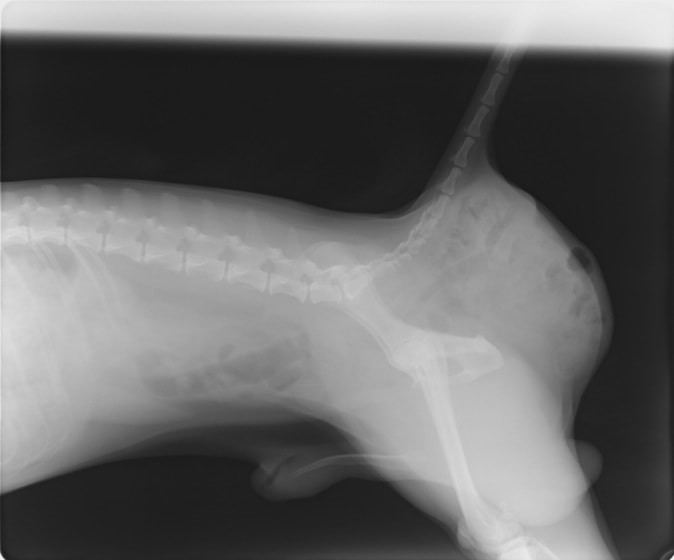

・ 胸部レントゲン検査:胸水貯留

・ 心エコー検査:異常なし

・ 胸水の性状:乳白色、TP:5.4g/dL、SG:1.038、TG:>500mg/dL、Tcho:65mg/dL、小リンパ球・好中球主体、細胞数:少ない

・ CT検査(リンパ管造影):無気肺以外の異常なし

レントゲン画像

除外診断より特発性乳び胸を疑い、大学病院にて外科手術(胸管結紮術、心膜切除術、乳び槽切除術、胸腔ドレーン留置)を実施しました。しかしながら胸水貯留が続いたため、再び麻酔下にて胸-腹腔シャントおよびリンパ管の結紮を行いました。